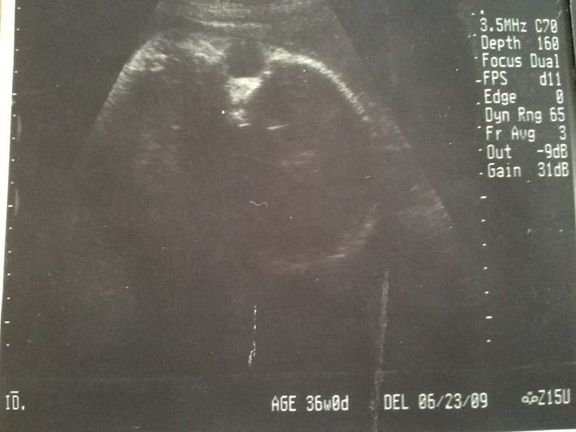

【応募すると全員もらえる】GELATO PIQUE エコー写真専用リフィルアルバム&エコー写真デジタルフレームが『初めてのたまごクラブ』冬号でもらえる!妊娠・出産

【応募すると全員もらえる】GELATO PIQUE エコー写真専用リフィルアルバム&エコー写真デジタルフレームが『初めてのたまごクラブ』冬号でもらえる!妊娠・出産 -

【応募すると全員もらえる】GELATO PIQUE エコー写真専用リフィルアルバム&エコー写真デジタルフレームが『初めてのたまごクラブ』秋号でもらえる!妊娠・出産

【応募すると全員もらえる】GELATO PIQUE エコー写真専用リフィルアルバム&エコー写真デジタルフレームが『初めてのたまごクラブ』秋号でもらえる!妊娠・出産 -